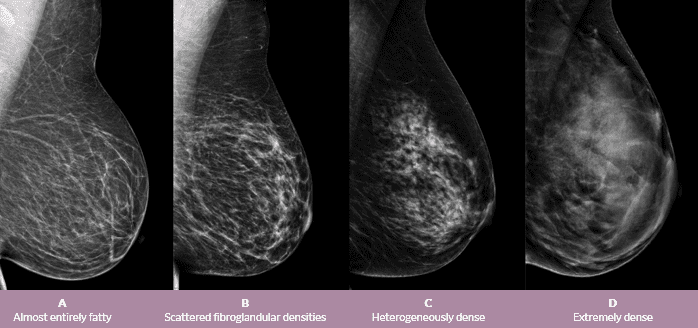

Awareness surrounding breast cancer is incredibly important as early detection, often through screening, can catch the disease when it is most treatable. Other symptoms of metastatic breast cancer can include fatigue, weight loss, and poor appetite, but it's important to remember these can also be caused by medication or depression. Local recurring breast cancer occurs when a new tumor develops in the breast that was originally affected. Overall, brain metastases occur in 15% to 24% of women with metastatic breast cancer. Elizabeth edwards was helping her husband campaign for vice president when she found her breast lump.